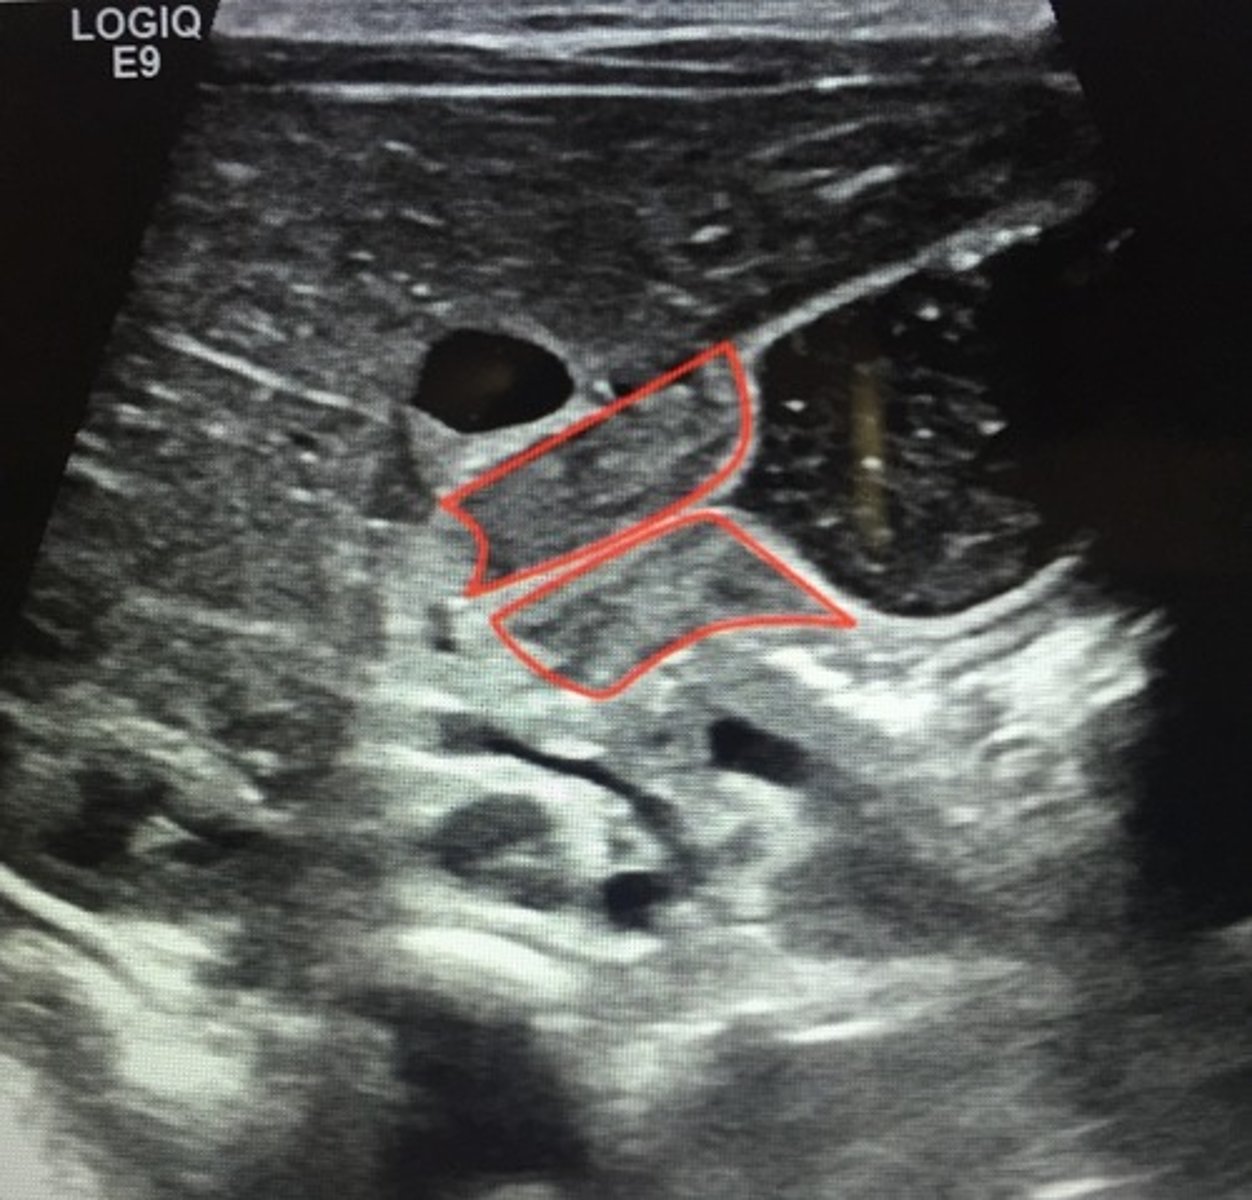

Recurrent UTIs in infants and children and one of the most common abnormalities is primary ___. Definitive diagnosis made via?

Vesicoureteral reflux (VUR)

- Contrast voiding cytourethrogram

- Renal US to screen hydronephrosis